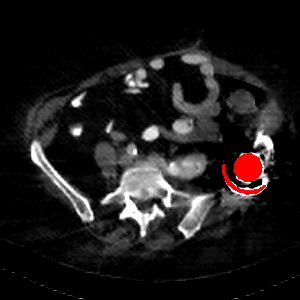

Visual comparison. As shown in Fig. 5, metallic implants such as spinal rods and hip prosthesis cause severe streaky artifacts and metal shadows, which obscure bone structures around them. cGan-CT cannot recover image intensity correctly for both cases. Sinogram domain or dual-domain methods perform much better than cGan-CT. LI, NMAR, and CNNMAR introduce strong secondary artifacts and distort the whole images. In NMAR images, there are fake bone structures around the metals, which is related to segmentation error in the prior image from strong metal artifacts. The segmentation error is also visible in NMAR sinogram. CNNMAR cannot restore the correct bone structures between rods in case 1. The tissues around the metals are over-smoothed in DuDoNet because LI sinogram and image are used as inputs, and the missing information cannot be inferred later. Our model retains more structural information than DuDoNet and generates anatomically more faithful artifact-reduced images.

Visual comparison. Fig. 7 shows two clinical CT images with metal artifacts. Case 1 is with moderate metal artifacts. cGan-CT does not suppress the artifacts completely and generates some fake details. LI, NMAR, CNN-MAR remove all the artifacts but introduce new streak artifacts, which is caused by the discontinuity in the corrected sinogram. DuDoNet outputs over-smoothed sinogram, which leads to blurred tissues close to the metal implants, such as muscle and bone. Only our model can provide realistic enhanced sinogram and remove the artifacts while retaining the structure of nearby tissues. Case 2 is very challenging as the rods bring strong metal shadows and bright artifacts around the vertebra. cGan-CT recovers the shape of vertebra but changes the overall image intensity. Other sinogram inpainting methods fail as the soft tissue and bone near the rods are heavily distorted. Our model removes part of the dark bands and reproduces correct anatomical structures around the rods.